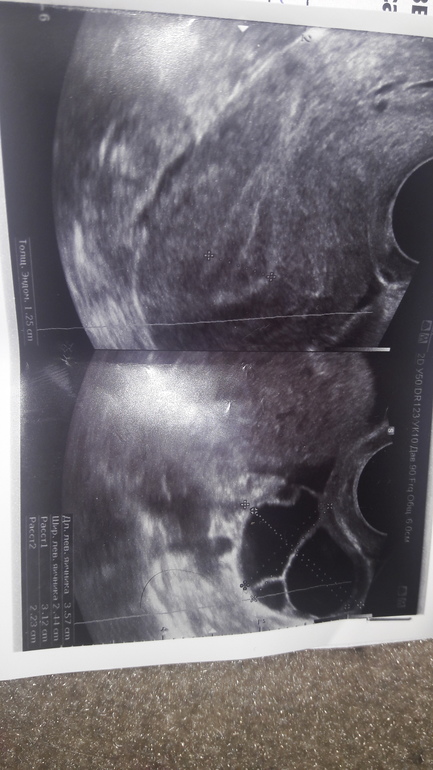

Девочки,неужели на яичнике киста?

Киста и не маленькая((. Да и эндометрий конечно многовато вырос.

вот у и меня 21 мм на 31мм...вот и думаю теперь с этого ли цикла она у меня,или уже давненько...

Да, киста, овуляции не было, фолик перерос в кисту. Не переживайте, в со цикле её уже не будет.